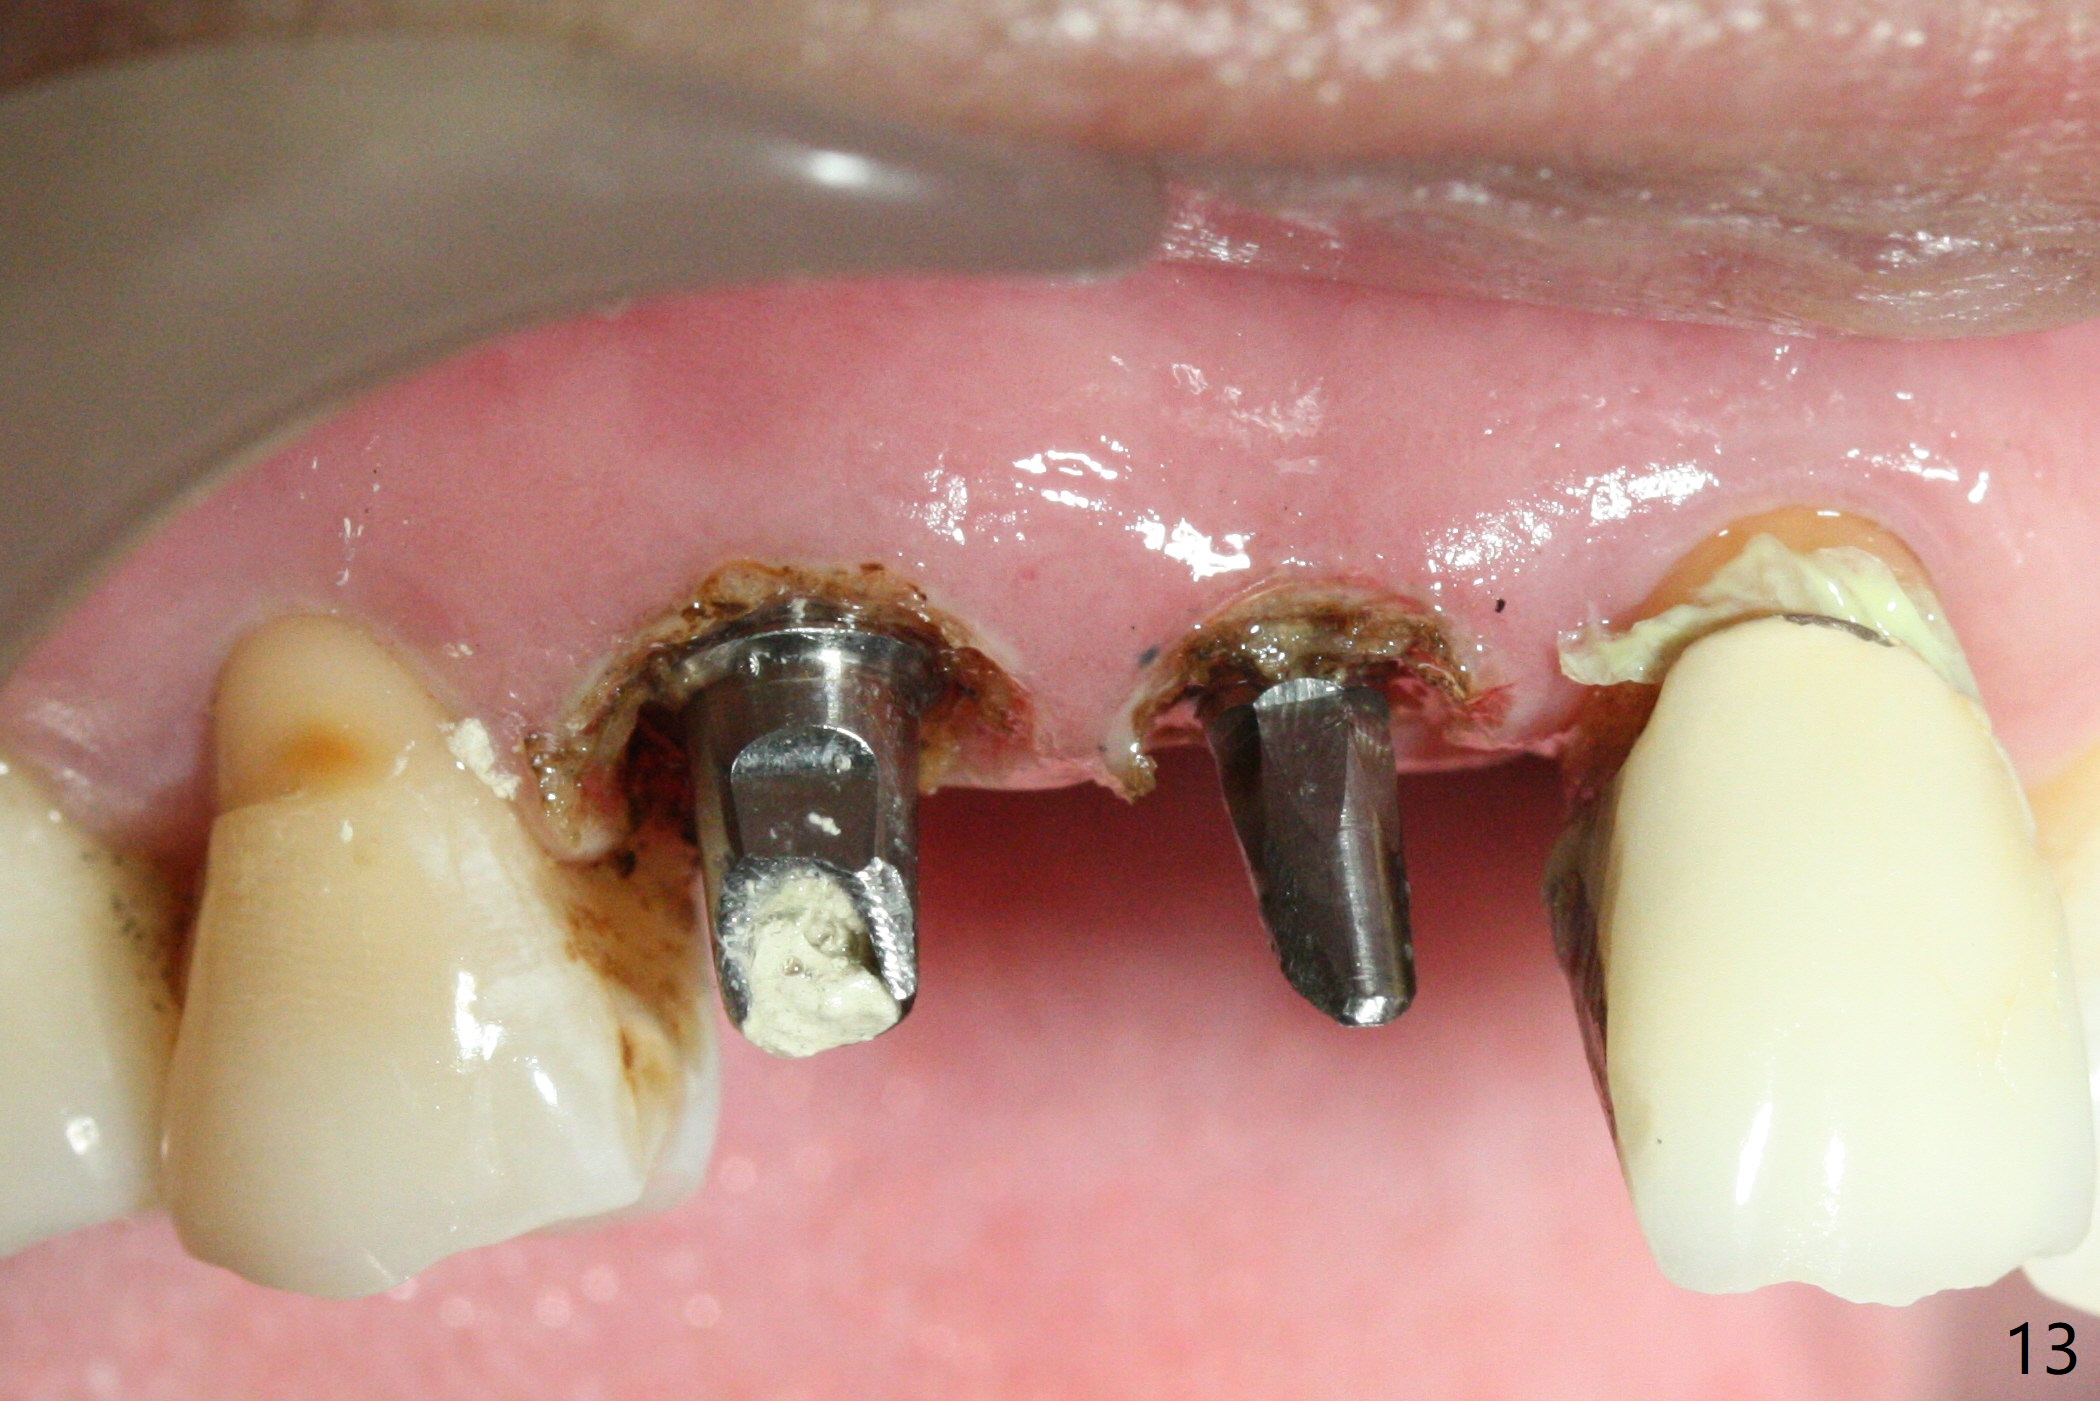

Since the ridge at #7 is ~ 4 mm, a 2.5x14 mm 1-piece implant is placed (Fig.8) after 1.2 mm (Fig.7), and 1.5 mm drills at 12 mm and 2 mm drill at 8 mm.  Later the implant is placed deeper (Fig.10).  There is no bone loss 7 or 12 months postop, respectively (Fig.11,12).  After Diode gingivectomy, there is papillary formation (Fig.13).  No provisional is provided after impression (with the abutment torqued at #6) for oral hygiene.  With access holes at #6 and 7, crowns are bonded with minimal residual cement (Fig.14 <, which is removed later).  There is no hard (Fig.15,16) or soft (Fig.17 *) atrophy 26 months postop, i.e., 13 months post cementation, due to the presence of socket shield (Fig.15 <, as compared to Fig.1).  In fact the tooth #8 has mobility and fremitus (short root/poor crown/root ratio, Fig.16); occlusal adjustment is done 13 months post cementation.  The crown is dislodged 2 years 1 month post cementation; a prefabricated post is being tried in (Fig.18).  There is no atrophy, bone loss or infection at #6 (with socket sheath (*)) or 7 two years 5 months post cementation (Fig.20-27).